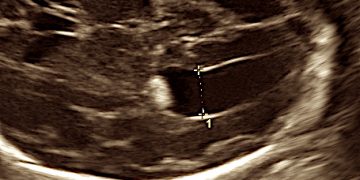

Guida al Counselling di Ottobre 2022: ridotta riserva ovarica e CFA

Cari colleghi, vi presentiamo la guida al counseling di Ottobre relativa alla ridotta riserva ovarica e alla conta dei follicoli antrali!! Potrete scaricarla cliccando sul link. Grazie a Carlotta Zorzi...